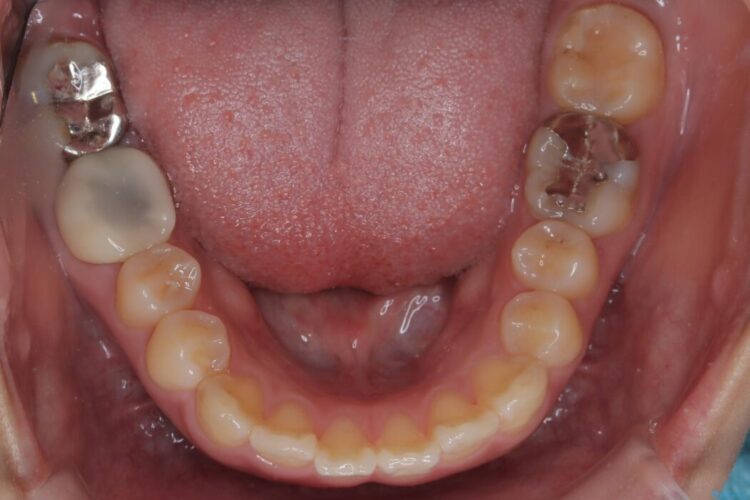

精密検査の結果、前歯を大きく後退させるスペースが必要と診断しました。

「前歯を下げたい」という患者様の強いご希望に応えるため、上下左右の第一小臼歯を抜歯。そのスペースを利用し前歯を奥へ移動させる治療計画を立案しました。

今回の矯正治療では、前歯を大きく後退させるスペースを確保するため、計画通り上下左右の第一小臼歯を抜歯しました。

装置には、上顎には目立たない裏側矯正(舌側矯正)を、下顎には透明な審美ブラケットを使用するハーフリンガル矯正を採用しました。抜歯によってできたスペースを最大限に活用し、前歯を効率よく後方へ移動。治療の結果、口元の突出感が大幅に解消され、Eライン(横顔の美しさの基準)も改善しました。人目を気にすることなく治療を完遂し、自信の持てる美しい横顔を獲得していただけました。